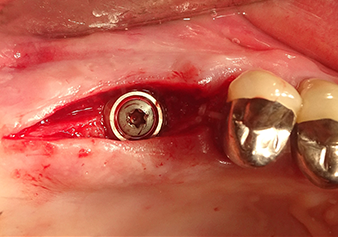

Following an intermediate check (Fig. 4) a further preparation step was performed (Fig. 5). Afterwards, the hydraulic Z35P instrument was used to lift the membrane to the desired position (Fig. 6 and 7). This was followed by further piezosurgical preparation of the implant bed, concluded with a rotary bur and shoulder milling cutter up to the implant diameter of 4.8 mm. Before the implant was inserted, the augmentation material (particle size approx. 0.8-1.6 mm) was introduced underneath the Schneiderian membrane (Fig. 8).

Implantation and prosthetic restoration

To move the augmentation material in the direction of the maxillary sinus atraumatically, the implant was inserted very slowly by hand (Fig. 9). In the process, the membrane was pushed in the cranial direction once again. After two months, the surgical site healed without irritation. Six months later, the x-ray check showed a significant increase in opacity as an indication of ossification (Fig. 10). The prosthetic restoration was carried out with a metal-ceramic crown.